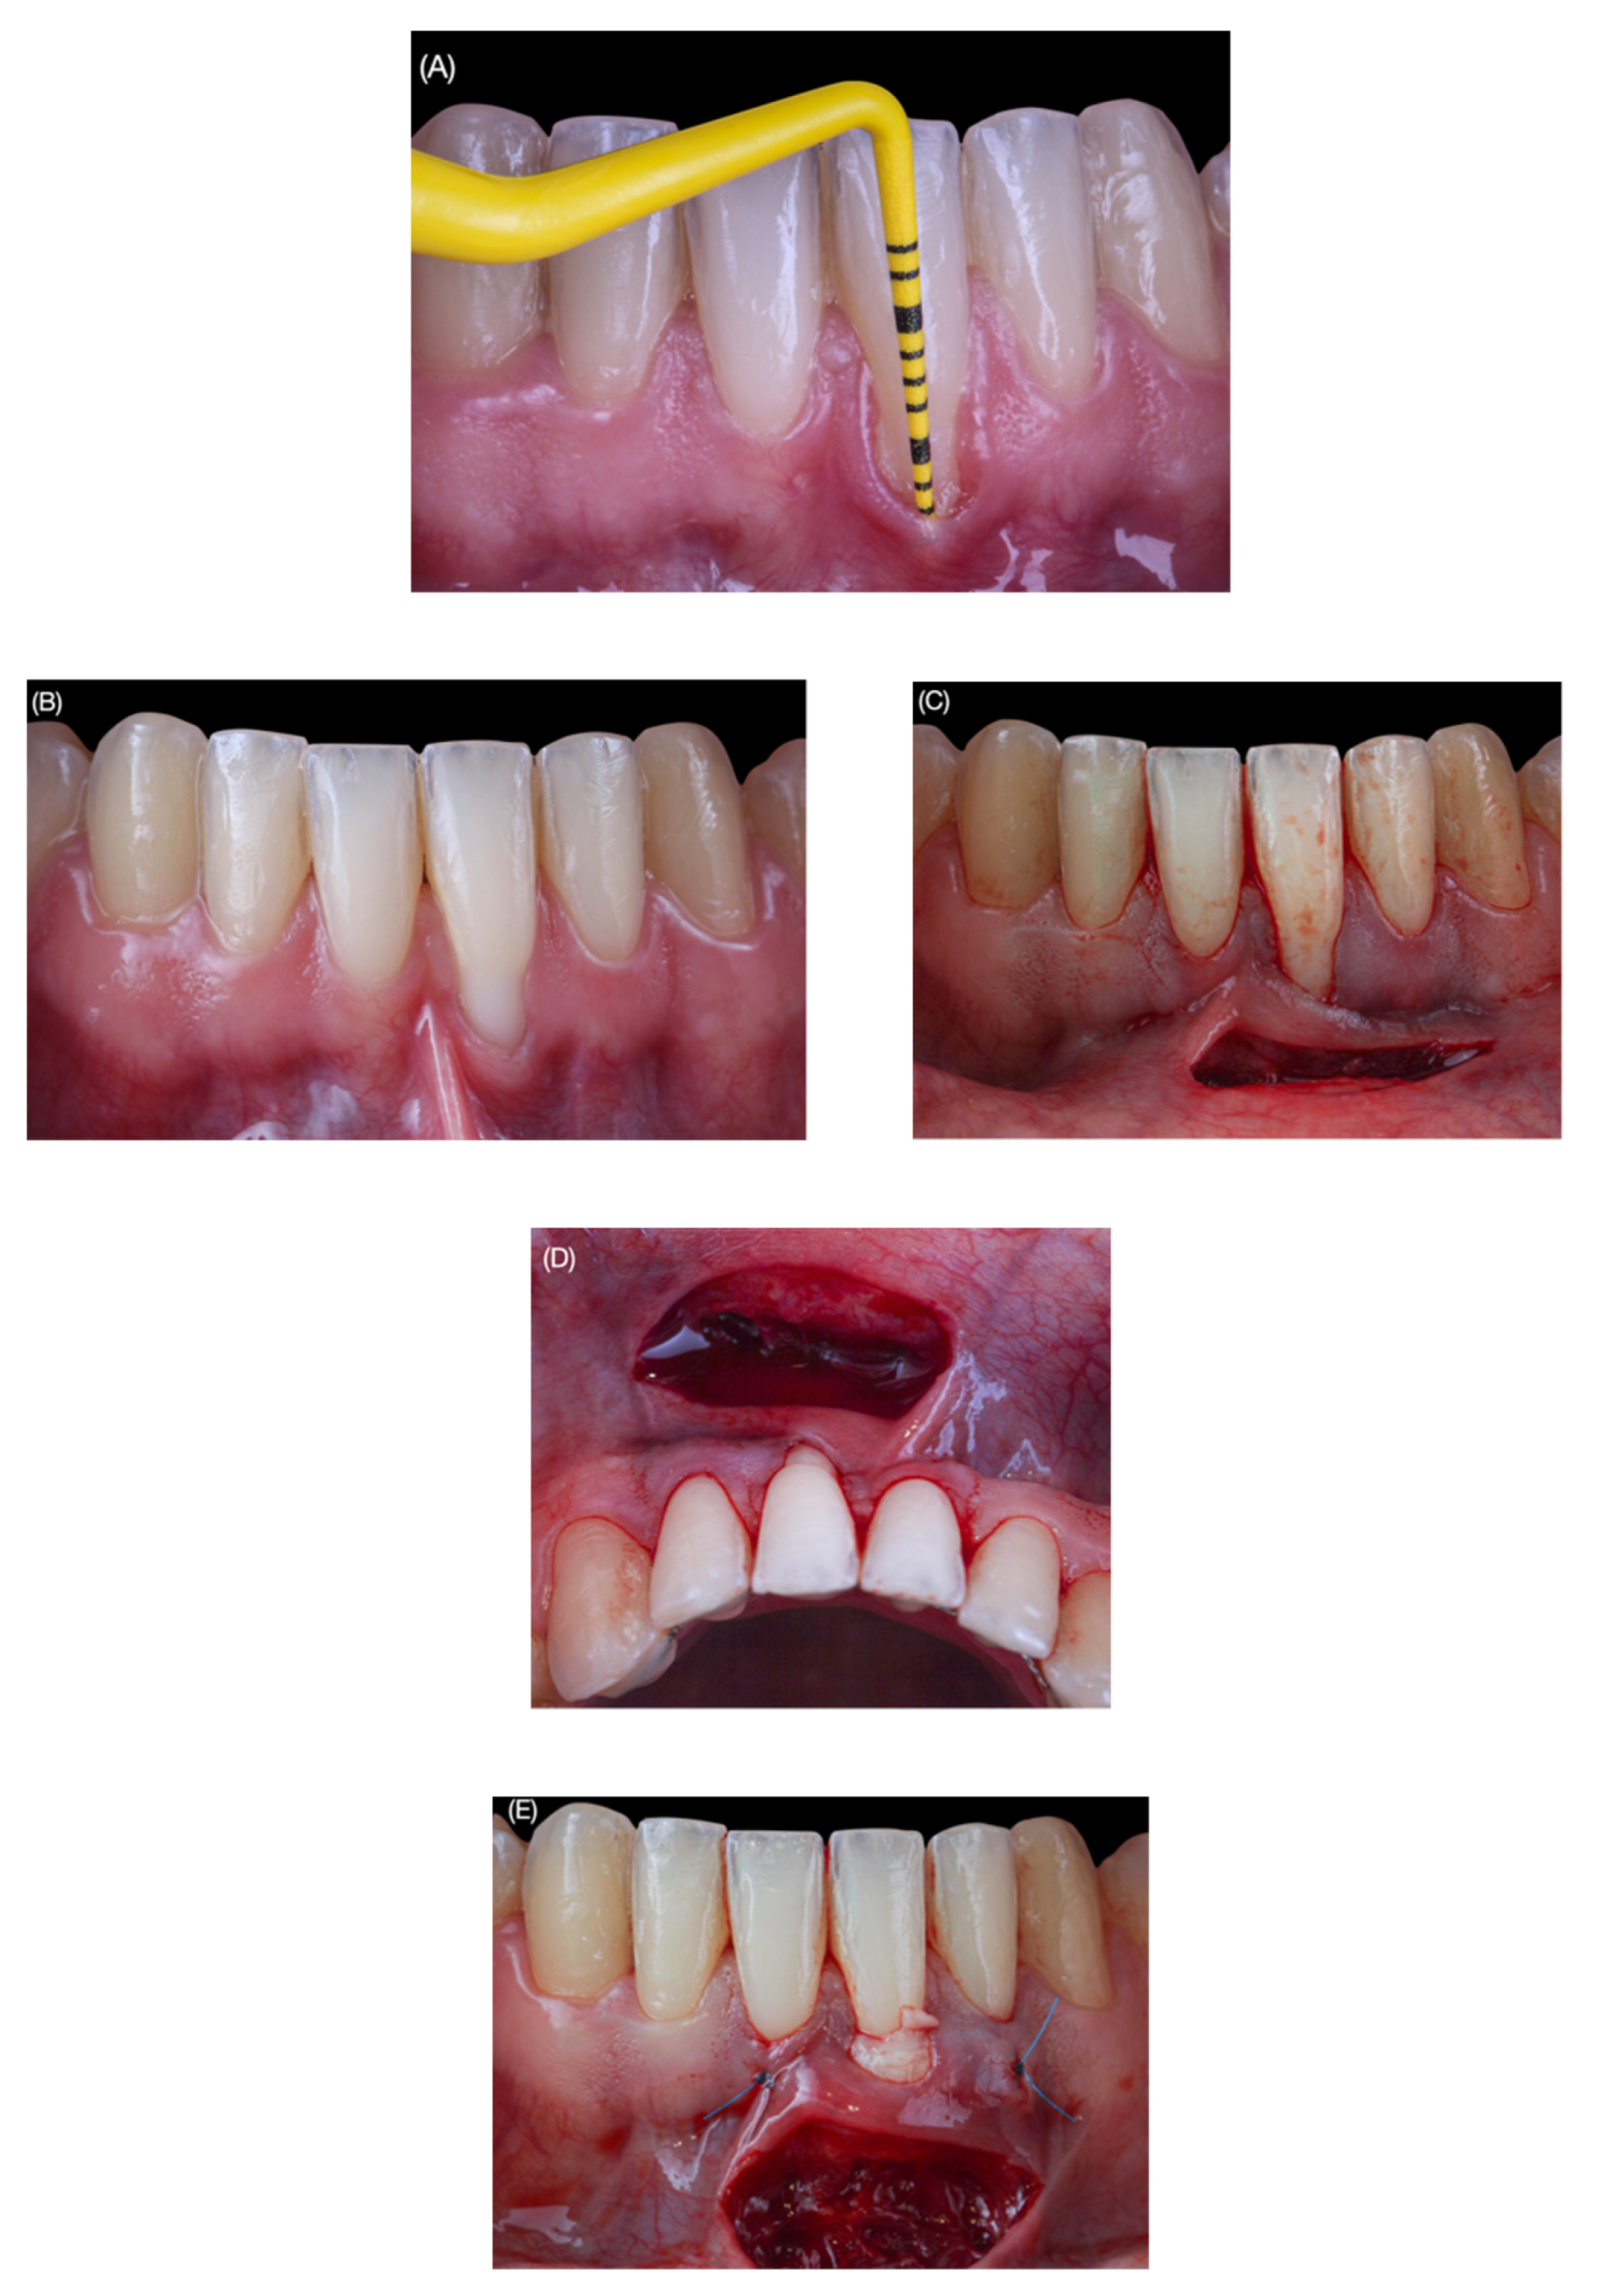

2.1. Surgical Protocol